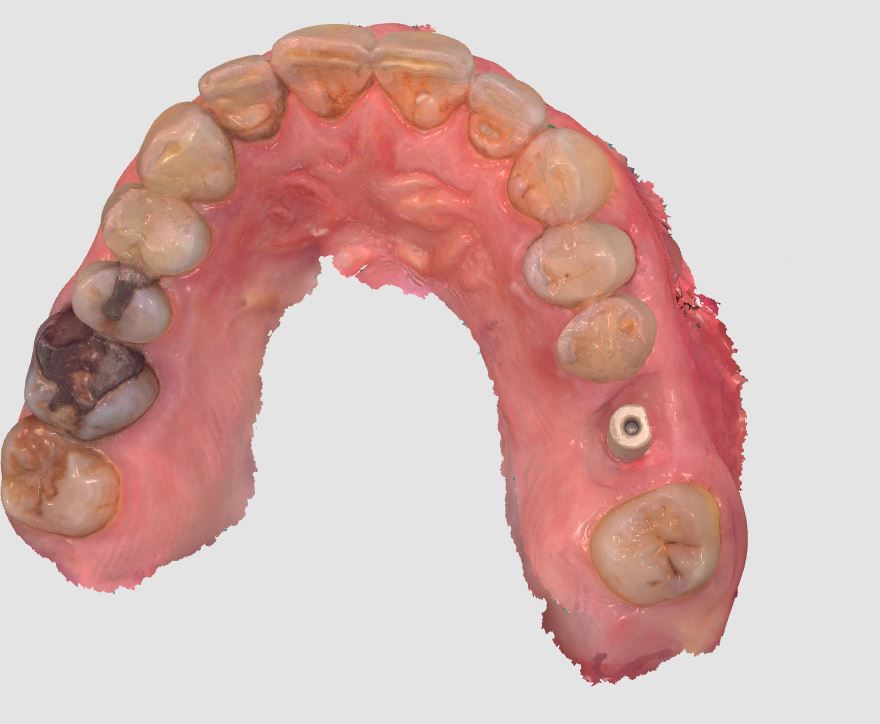

10a. 10b. 10c. 3D scans and radiograph control of the implantplacement.

10a

10b

10c

12a. 12b. 12c. 12d. Digital files after intra-oral scanning showing the gingival contouring for the prosthetic phase 4 months post implant placement.

12a

12b

12c

12d